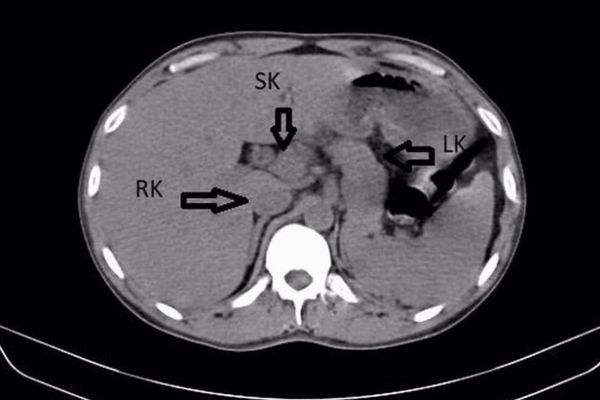

しかもその後、腹部の超音波検査とCTスキャンにより、男性に第3の腎臓が存在することが明らかにされた。

通常、腎臓は左右に1つずつあるが、この男性には「過剰腎(supernumerary kidney)」と呼ばれる第3の腎臓が右の腎臓と癒着し、馬蹄形をしていたという。